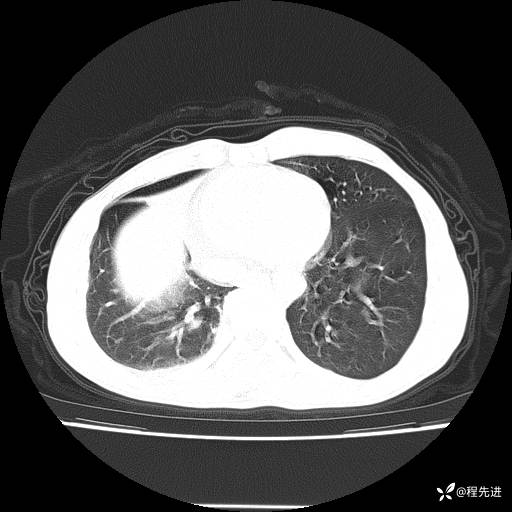

患者性别:男

患者年龄:49岁

主诉:咳嗽、胸痛1周

简要病史:1周前受凉感冒后开始出现咳嗽症状,阵发性连声咳,痰多,黄白痰,不易咳出,伴胸痛、气紧、胸闷,右侧为主,活动用力、呼吸时胸痛明显,曾在当地诊所贴敷膏药仍疼痛

体格检查:T:36.3 ℃ P:80 次/分 R:20 次/分 BP:120/88 mmHg,指脉氧饱和度97%,意识清晰,呼吸平稳,右侧第二、三肋骨压痛,可见膏药贴敷,皮肤无异常,双肺呼吸音粗,未闻及干湿性啰音。心率80次/分,节律整齐,无杂音。腹平软,全腹无压痛无反跳痛

临床诊断:社区获得性肺炎

CT平扫: